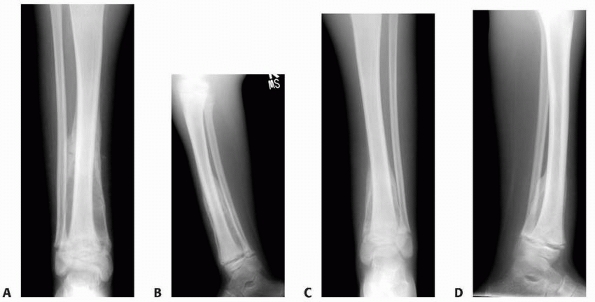

FIGURE 6-5 A 6-year-old boy presented with shoulder pain after a fall. Anteroposterior (A) and lateral (B)

radiographs of the right proximal humerus show a pathologic fracture through a well-defined, lytic lesion in the proximal humeral metaphysis. The fracture presented some comminution that gave the appearance of fallen leaf sign (arrow). This lesion was consistent with unicameral bone cyst and conservative treatment with a fracture brace and sling was initiated. Six weeks after the injury, radiographs (C,D) show consolidation of the fracture and healing of the cyst. The patient was symptom free and returned to full physical activities. (Figures reproduced with permission from The Childrens Orthopaedic Center, Los Angeles, CA.) |